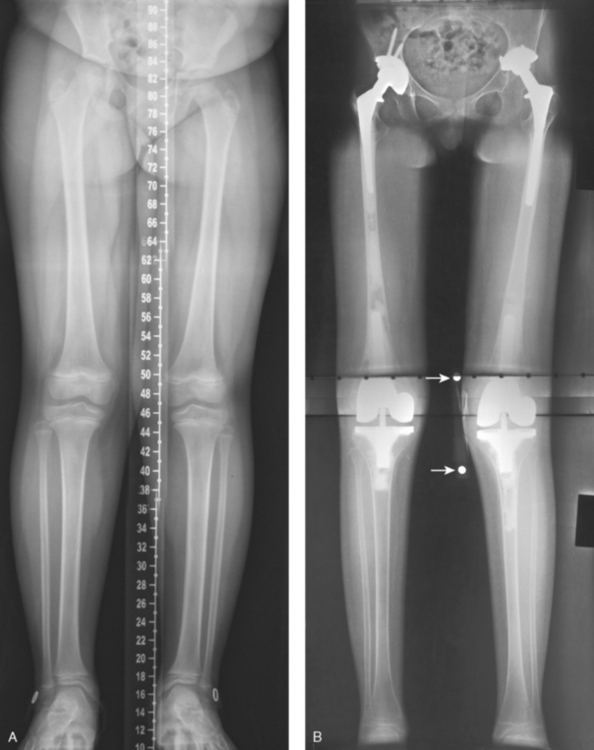

Structures shown: This projection shows the entire right and left limbs from the hip joint to the ankle joint (Fig. 6-173).

Fig. 6-173 Lower limbs: hips, knees, and ankles. A, Computed radiography (CR) “stitched” image. Computer created one image from three separate CR plates within a 51-inch (130-cm) IR. Note centimeter scale created within the image. B, A 51-inch (130-cm) radiographic film image. Arrows point to magnification marker taped to knee for measurements.